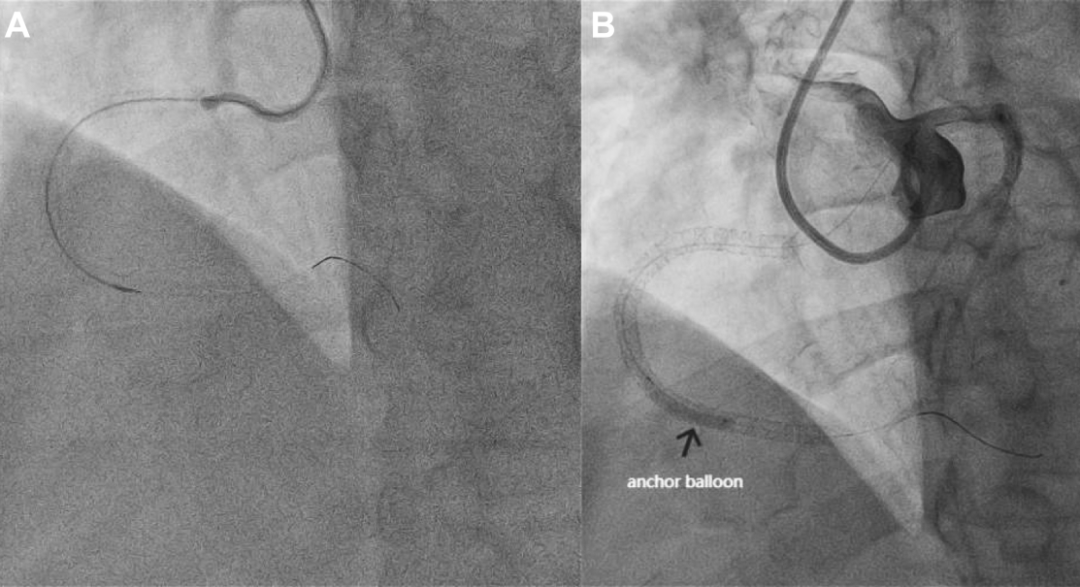

术者首先采用正向导丝升级技术。通过桡动脉入路,将7F AL 0.75指引导管送至RCA开口处,在135cm CorsairPro微导管的支持下,依次使用Pilot 200、Bingoreach 6和Conquest Pro导丝尝试正向通过CTO病变,但所有导丝均进入内膜下(图2A)。

图2 正向导丝无法进入真腔

(A)正向导丝升级技术未能通过CTO病变。(B)在RCA内用锚定球囊锚定正向导丝后,将AL 0.75指引导管转至左冠开口,随后造影证实正向导丝位于内膜下。

经过约30分钟的尝试后,正向途径终因无法进入真腔而被迫放弃。

第一步:锚定支撑,建立稳定的单导管操作平台

术者没有撤出位于RCA内的正向指引导管系统,而是沿正向导丝将一个球囊送至RCA远端并充盈,形成锚定支撑。

这个球囊提供了足够的支撑力,使得AL 0.75指引导管能够安全地从右冠开口脱出,并重新稳定地钩挂到左冠脉开口。

通过这根现在位于左冠开口的指引导管进行对侧造影,确认了此前正向导丝确实位于RCA的内膜下(图2B,视频1)。